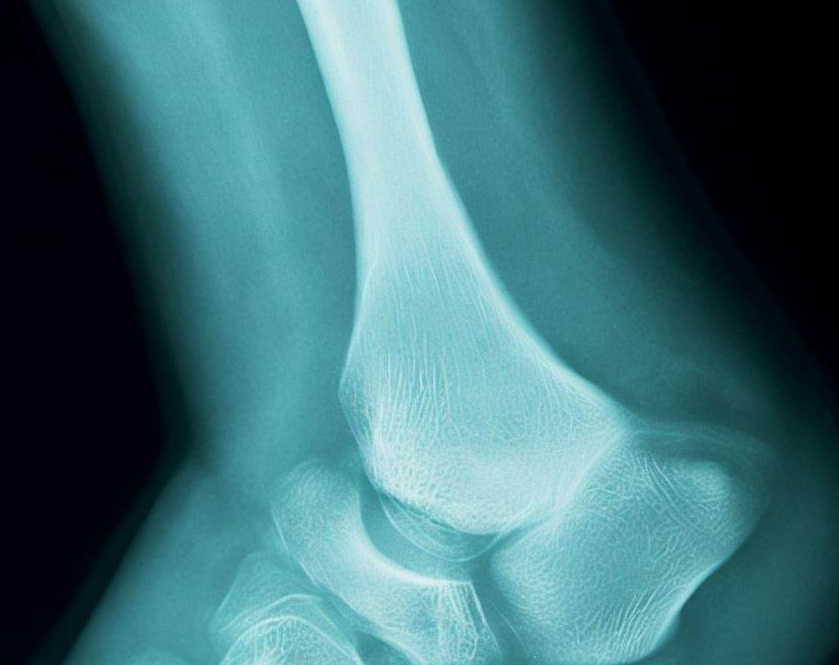

A rare bone disorder characterized by the spontaneous onset of tarsal navicular osteonecrosis in adults. Patients mostly complain about midfoot and hindfoot pain that persists despite treatment, as well as midfoot edema and tenderness over the dorsomedial aspect, a collapsed medial longitudinal arch, and pes planovalgus. The comma-shaped deformity is shown on X-rays when the lateral aspect of the navicular bone collapses, causing the medial or dorsal aspect of the bone to protrude. This syndrome, which is associated with pathological fractures, can be bilateral or asymmetric. The most constant clinical symptoms of MWS (Mueller-Weiss syndrome) are a heel varus deformity and discomfort that occurs in the fifth decade.

The navicular bone, located in the center of the foot, is a half-moon or boat-shaped bone. If it abruptly loses its blood supply, bone tissue begins to die, causing the joint to erode and the bone to eventually collapse.